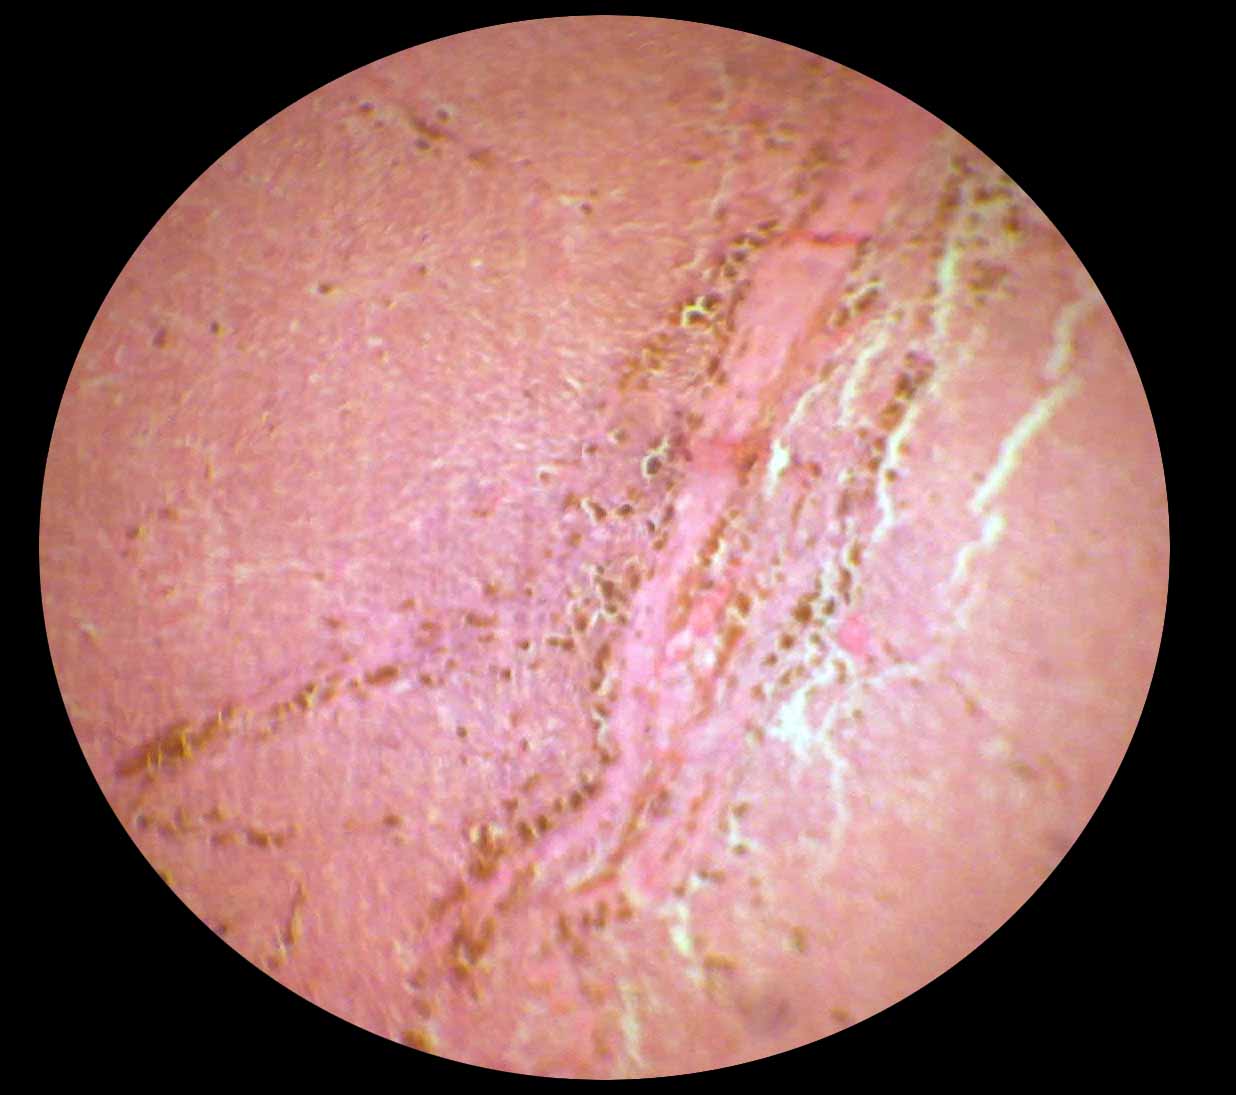

Chronic Lymphocytic Leukemia Microscopic View

Images of Chronic Lymphocytic Leukemia Microscopic View

Chronic Lymphocytic Leukemia Microscopic View Images